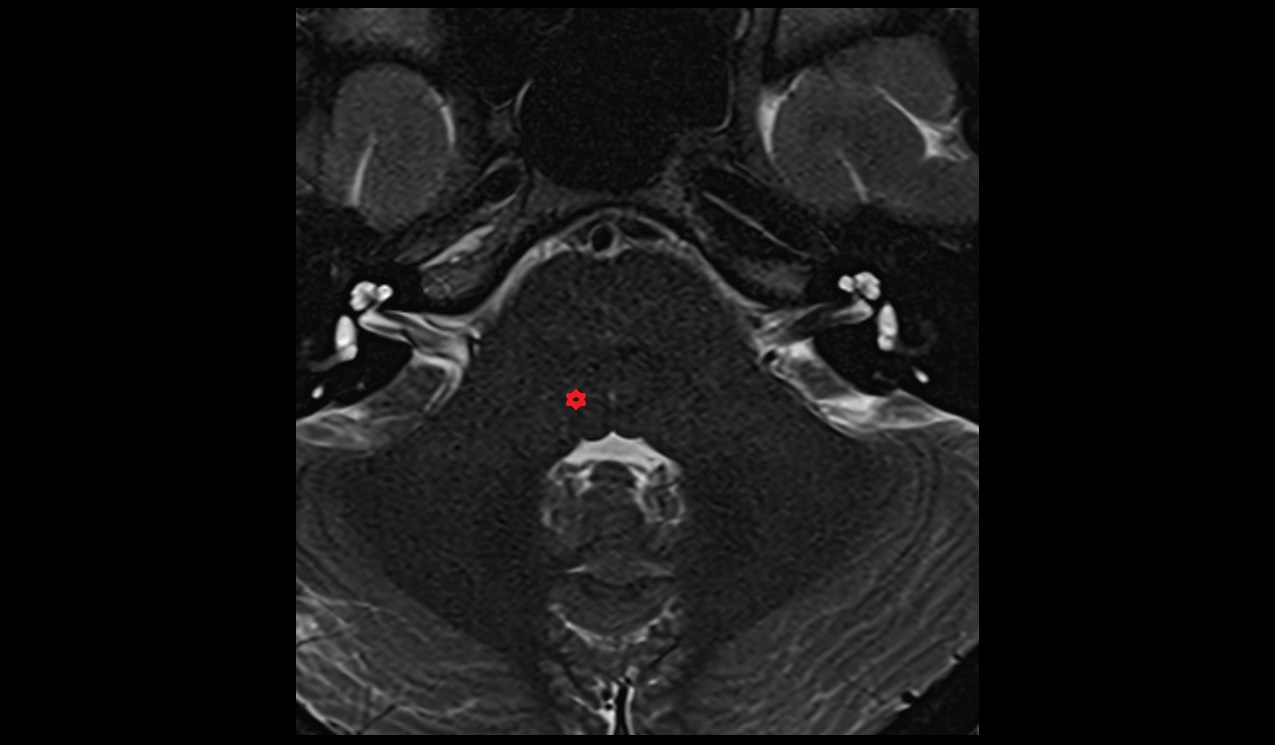

- Peripheral zone of prostate

- Anterior Fibromuscular Stroma of prostate

- Central zone of prostate

- Transitional zone of prostate